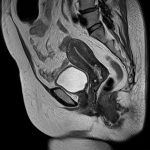

Hình ảnh giải phẫu MRI tiểu khung nam & nữ.

Axial / Coronal / Sagittal.